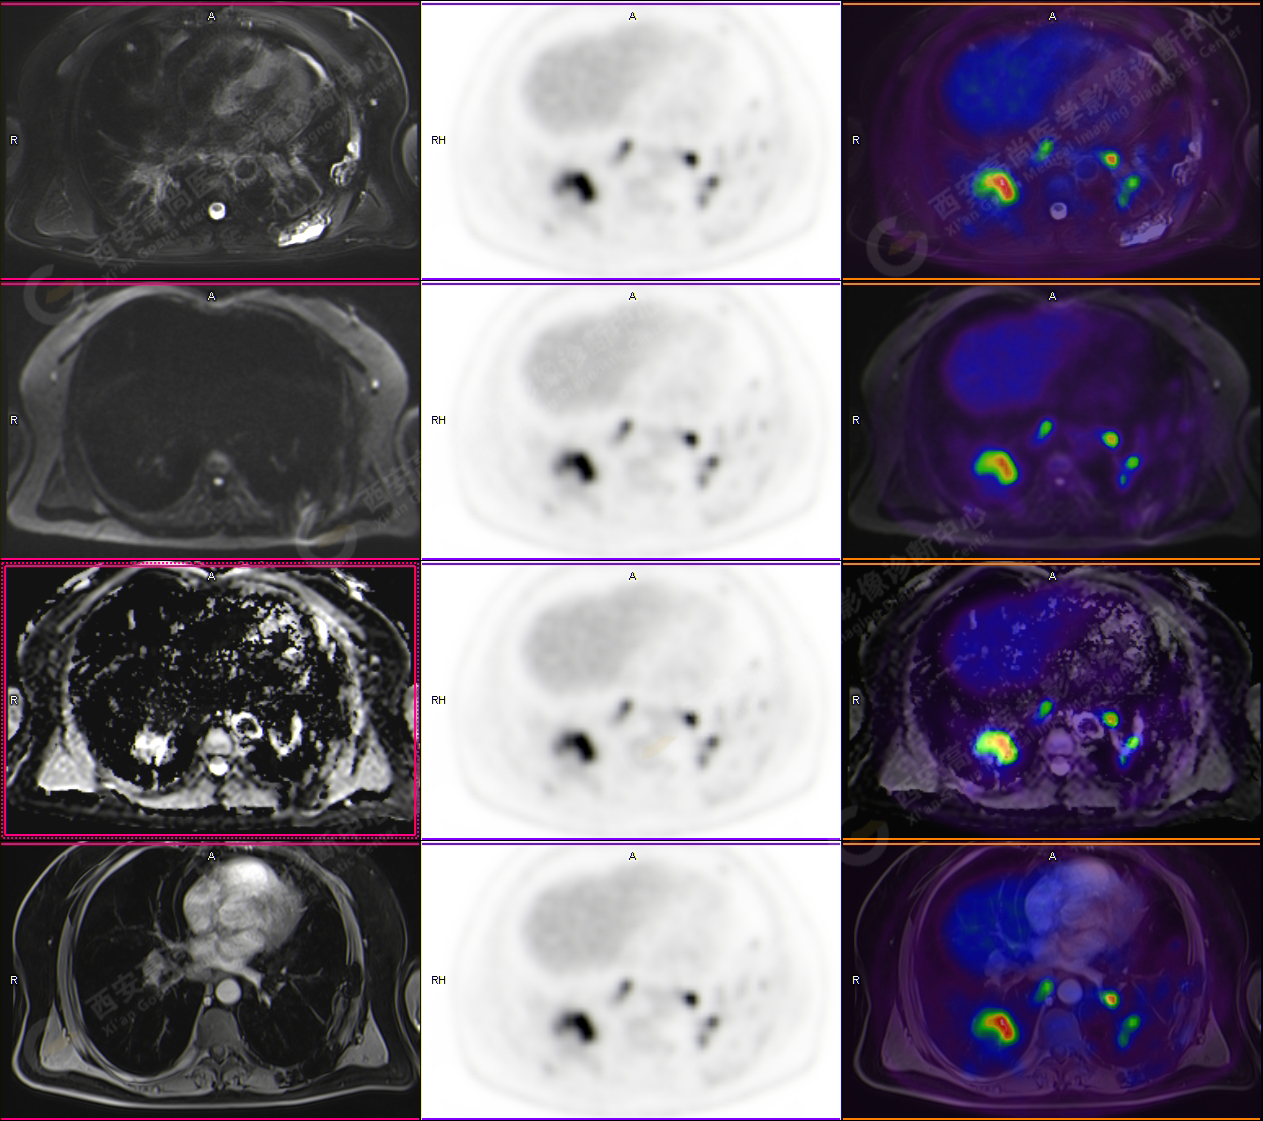

男性,53歲,頭暈半月入院,CT發(fā)現(xiàn)肺內(nèi)腫塊,雙肺多發(fā)大小不等實(shí)性及粟粒樣結(jié)節(jié),雙肺門(mén)及縱隔多發(fā)腫大淋巴結(jié)。病程中無(wú)發(fā)熱、胸悶氣及胸部不適。既往:左側(cè)肋骨外傷史。

PET-MR圖像